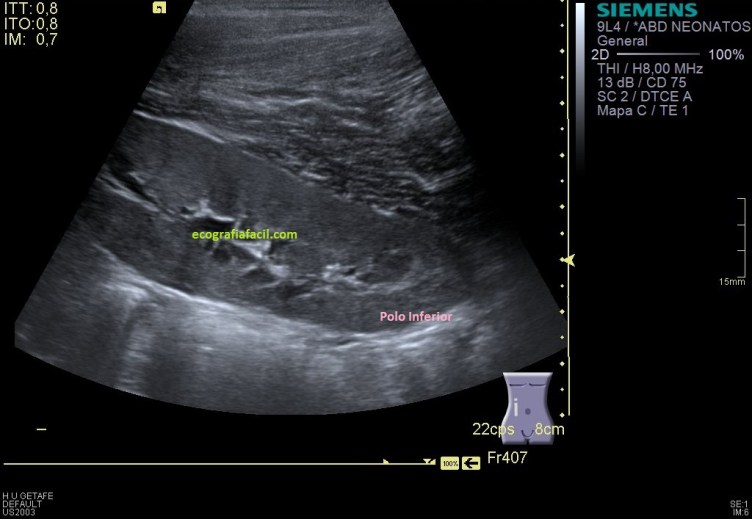

Como en la imagen 1 no he podido ver los polos, tengo que poder demostrarlos aunque tenga que estudiarlos de modo individual, polo superior en una,imagen 2 y polo inferior en otra, imagen 3.

En el lado izquierdo no encontré el riñón en su localización normal, en decúbito prono, ya sabía que era ectópico, tuve que colocar a la paciente en decúbito supino y buscarlo pélvico, junto a la región umbilical se encuentra el RI, malrotado (posición anómala) de características normales morfológicamente hablando, observo polo inferior, pero no del todo, eso lo hago como puedes ver en la imagen 6.

Hago corte axial, la imagen no es limpia, es un riñón ectópico y malrotado, no vamos a conseguir una imagen perfecta…